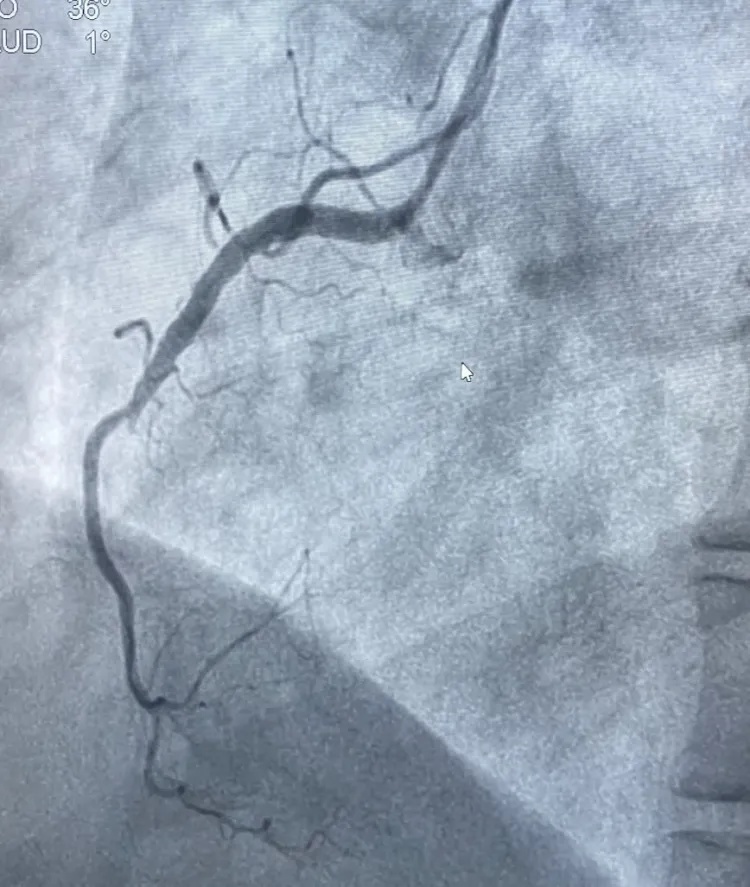

情况紧急,胸痛中心迅速响应,在与家属沟通并签署知情同意书的同时,同步办理住院手续,全程开通绿色通道,最快的速度把吕女士送入导管室接受急诊PCI治疗(经皮冠状动脉介入治疗)。在王宁夫主任医师指导下,徐鹏和钱宇峰副主任医师为她进行介入治疗,术中发现她的右侧冠状动脉近段完全闭塞,通过球囊扩张并植入支架,成功开通了堵塞的血管,恢复了心肌供血。

术前右冠中段完全闭塞

术后右冠完全开通